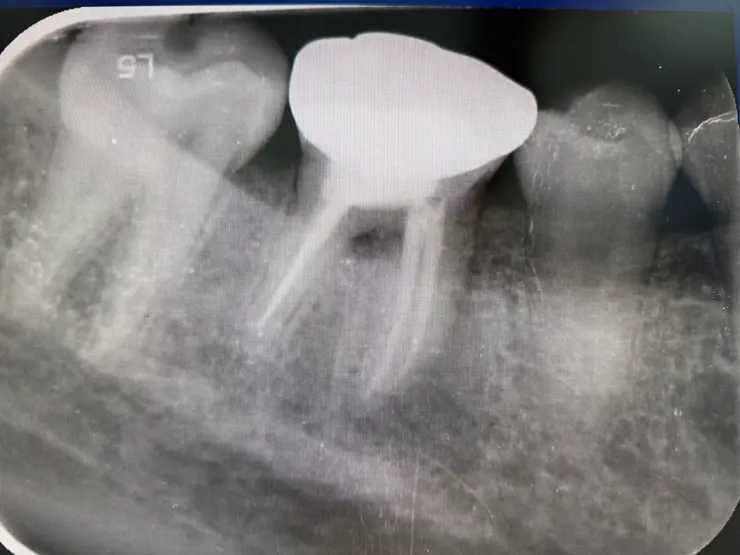

環口X光

單張X光